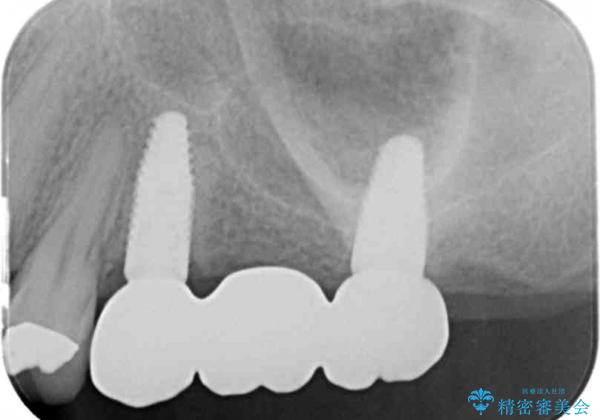

- 110万円(インプラント×2・チタンカスタムアバットメント×2・ジルコニアクラウン×3・仮歯×3)費用は治療当時の料金となります

しっかりと噛めるようになったことで、また食事を楽しんでいただくことができるようになりました。